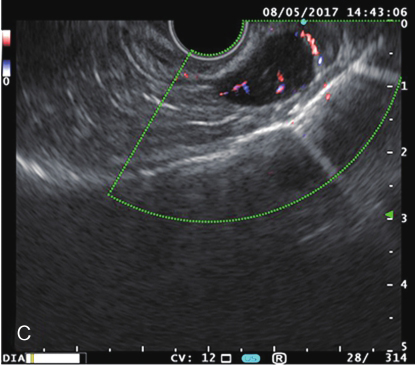

全腹增强CT:胃底软组织结节,考虑胃间质瘤可能,建议结合胃镜检查;肝顶多发小囊肿(图2)。

图2腹部增强CT